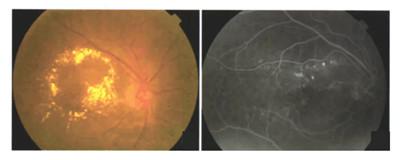

临床上8种治疗糖尿病性黄斑水肿(DME)的药物

糖尿病性黄斑水肿(Diabetic Macular Edema,DME)是比较常见的糖尿病眼底病变,属于糖尿病并发症糖尿病性视网膜病变(DR)是视网膜中心区域积液,导致黄斑肿胀和变厚,从而...

7种治疗糖尿病性黄斑水肿(DME)的药物

糖尿病性黄斑水肿(Diabetic Macular Edema,DME)是由糖尿病引起的发生在眼睛视网膜黄斑区的慢性并发症,是导致糖尿病患者视力损害,甚至失明的最常见原因之一。 ...